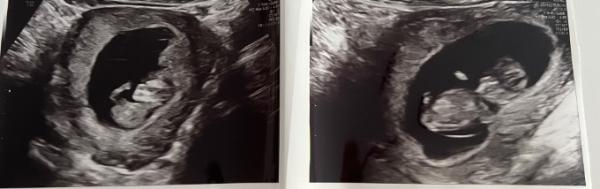

Wir hatten im Februar eine künstliche Befruchtung die gescheitert ist und im Juni 2 Wochen nach unserer Hochzeit hielt ich einen positiven Test in der Hand und bin nun in der 12. SSWoche